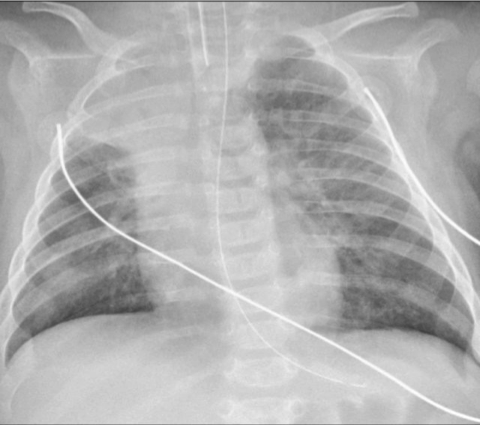

Chest radiograph of a 3-month-old infant with severe RSV bronchiolitis: demonstrating a collapsed right upper lobe, hyperinflated left lung and bilateral perihilar, peribronchial thickening. The patient is intubated and has a nasogastric tube in situ.